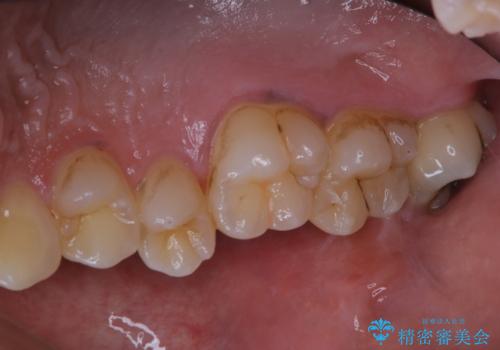

タバコによる着色をPMTCできれいな白い歯に

- タバコによる着色を綺麗にしたいとのことで来院されました。PMTC60分コースを行いました。

タバコに含まれているものの中で、タールというものが歯の黄ばみの原因です。その黄ばみなどを、無理に落とそうとしたりすると歯の表面に傷がついてしまったり余計に汚れがつきやすい状態になることがあります。

PMTCでは、歯の表面の凸凹にミネラルを補給して、ツルツルの表面に仕上げます。定期的にPMTCを行うことにより、歯質の強化になり着色がつきにくい状態になります。